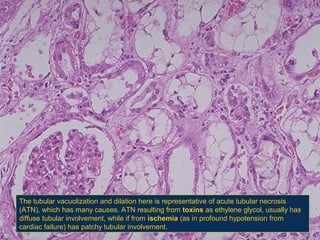

The tubular vacuolization and dilation here is representative of acute tubular necrosis

(ATN(, which has many causes. ATN resulting from toxins as ethylene glycol, usually has

diffuse tubular involvement, while if from ischemia (as in profound hypotension from

cardiac failure( has patchy tubular involvement.